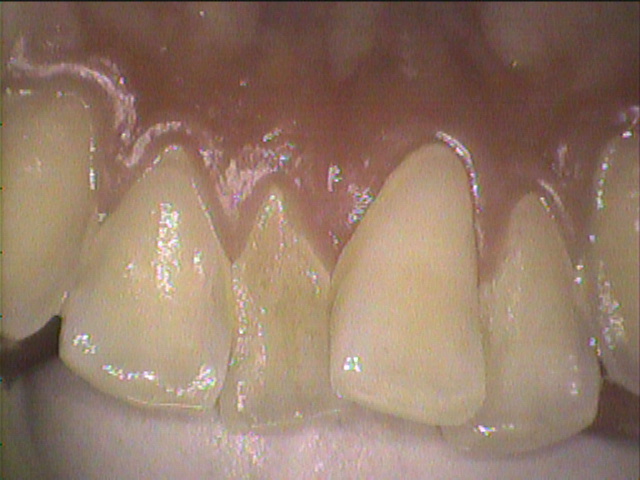

◎クリーニング前

フロスをほとんど使えていなかったそうで、歯間部にプラーク(歯垢)と歯茎に炎症がありました。

歯と歯が重なっているところは歯ブラシが当たりづらいため、歯石やプラーク(歯垢)がつきやすい場所です。